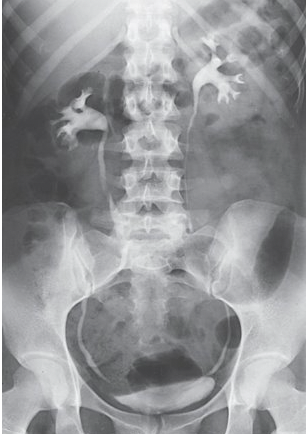

What is this projection?

AP